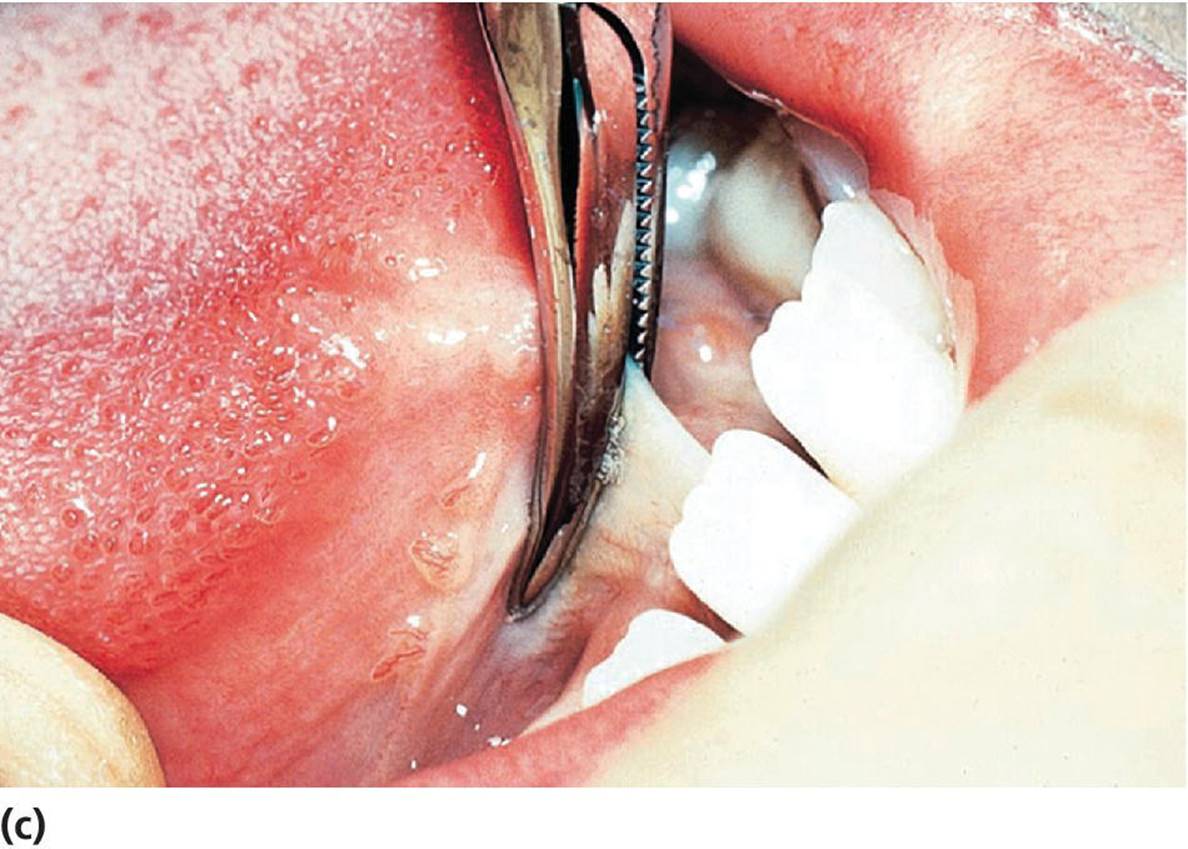

If a lingual frenulum is frequently traumatized by the mandibular incisors, causes retraction of the lingual gingiva or the mandibular incisors, or interferes with nourishment, speech development, or hygiene procedures it should be cut. It is vital to avoid two structures in this region, being the submandibular duct and the sublingual vein. The dissecting cut is best made lingual to the caruncles, parallel to the undersurface of the tongue, taking care not to go too deep (Figure 15.31).

Figure 15.31 Lingual frenuloplasty. (a) Lingual frenulum restricting the movements of the tongue. (b) Local anesthesia. (c) Curved hemostat is placed close to the tongue. (d, e) Frenulum is cut. (f) Healing after 10 days.